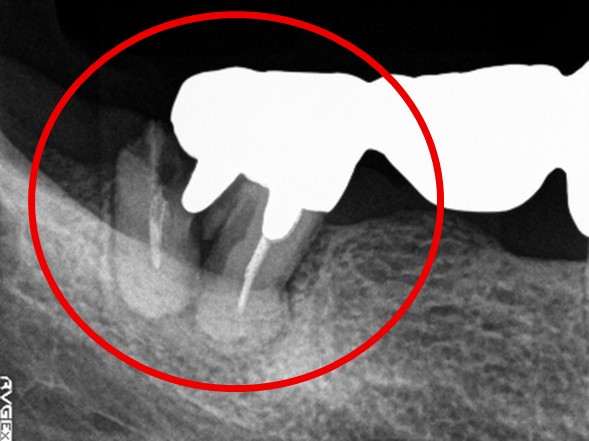

右下奥の歯が、グラグラして噛むと痛い。

治療内容

歯根の周りの骨が全く無い状態でしたので、保存することができず抜歯しました。3本歯がないところに2本インプラントを埋入しました。

Before

※赤丸を抜歯しました。

After